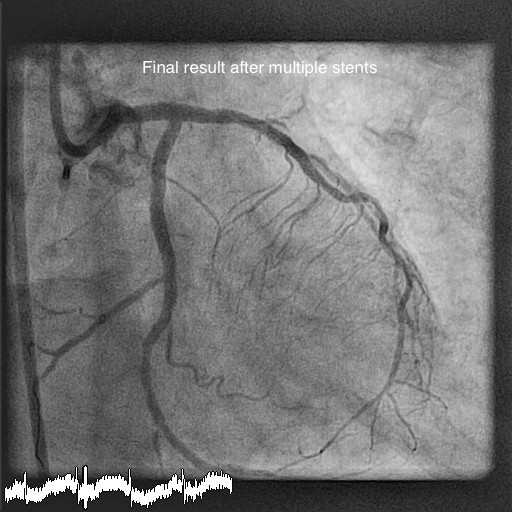

A 65 yr old gentleman with chest pain and severe breathlessness was admitted in his local hospital. He was not able to walk for more than 5 minutes. He was initially treated with medicine and then underwent a coronary angiogram in their hospital. His angiogram showed block in all 3 blood vessels in heart and his heart pumping was also weak on echocardiogram (echo scan). He was transferred to Apollo main hospital, Greams Road in Chennai for further treatment. His angiogram pictures were reviewed by the heart team (both cardiologist and cardiac surgeon included) and was considered to be high risk for open heart surgery (bypass surgery) because of the weak heart. Therefore it was decided to do a complex angioplasty called Rotablation to clear the hardened chalk material and then use stents (ring) to improve blood supply to the heart. However, considering his weak heart he also would need an artificial balloon in his major blood vessel (Intra-aortic balloon pump- IABP) to help support the heart during the procedure.

The patient underwent the procedure with Rotablation and stenting with the support of IABP and temporary pacemaker wire. Drilling was done successfully and 5 stents were used to clear the blockages in the coronary arteries starting from the main artery in the heart. The patient stayed in hospital for 48 hrs and then he was discharged home. He felt remarkably better after the procedure and in 1 month his heart function improved well. He was able to walk 45mins to 1 hour without any problem. He doesn’t have any more chest pain or breathlessness.